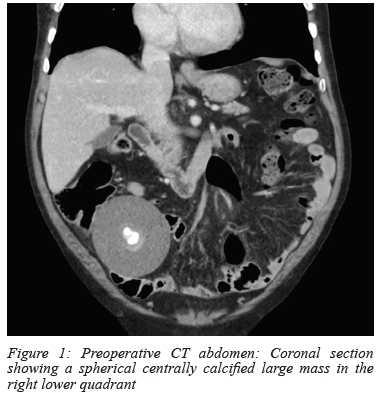

His abdominal radiographs showed calcifications in the pelvis that were thought to be phleboliths. His baseline blood tests showed no anaemia, normal renal function and normal value tumour markers. An outpatient upper endoscopy and colonoscopy were normal. A CT abdomen was then requested, which showed a well-defined mass measuring 6.74 x 7.9 x 8.18 cm, with a central area of calcification with a differential diagnosis of a teratoma or non-benign lesion (Figure 1).

Due to the uncertainty of diagnosis and suspicion of non-benign lesion, the patient was counselled and consented for an explorative laparotomy. Intraoperative findings revealed a large, smooth, firm white ovoid mass located in the left upper quadrant, not attached to any intra-abdominal structures, with normal solid organs and hollow viscera. No intra-abdominal fluid or lymph nodes were noted. The 90 mm diameter 245.3 g mass (Figure 2) was removed and sent for histology to exclude malignancy. The histology showed a hyalinised acellular mass calcified centrally with no evidence of malignancy, in keeping with a diagnosis of a giant loose peritoneal body1 (diameter more than 5 cm).